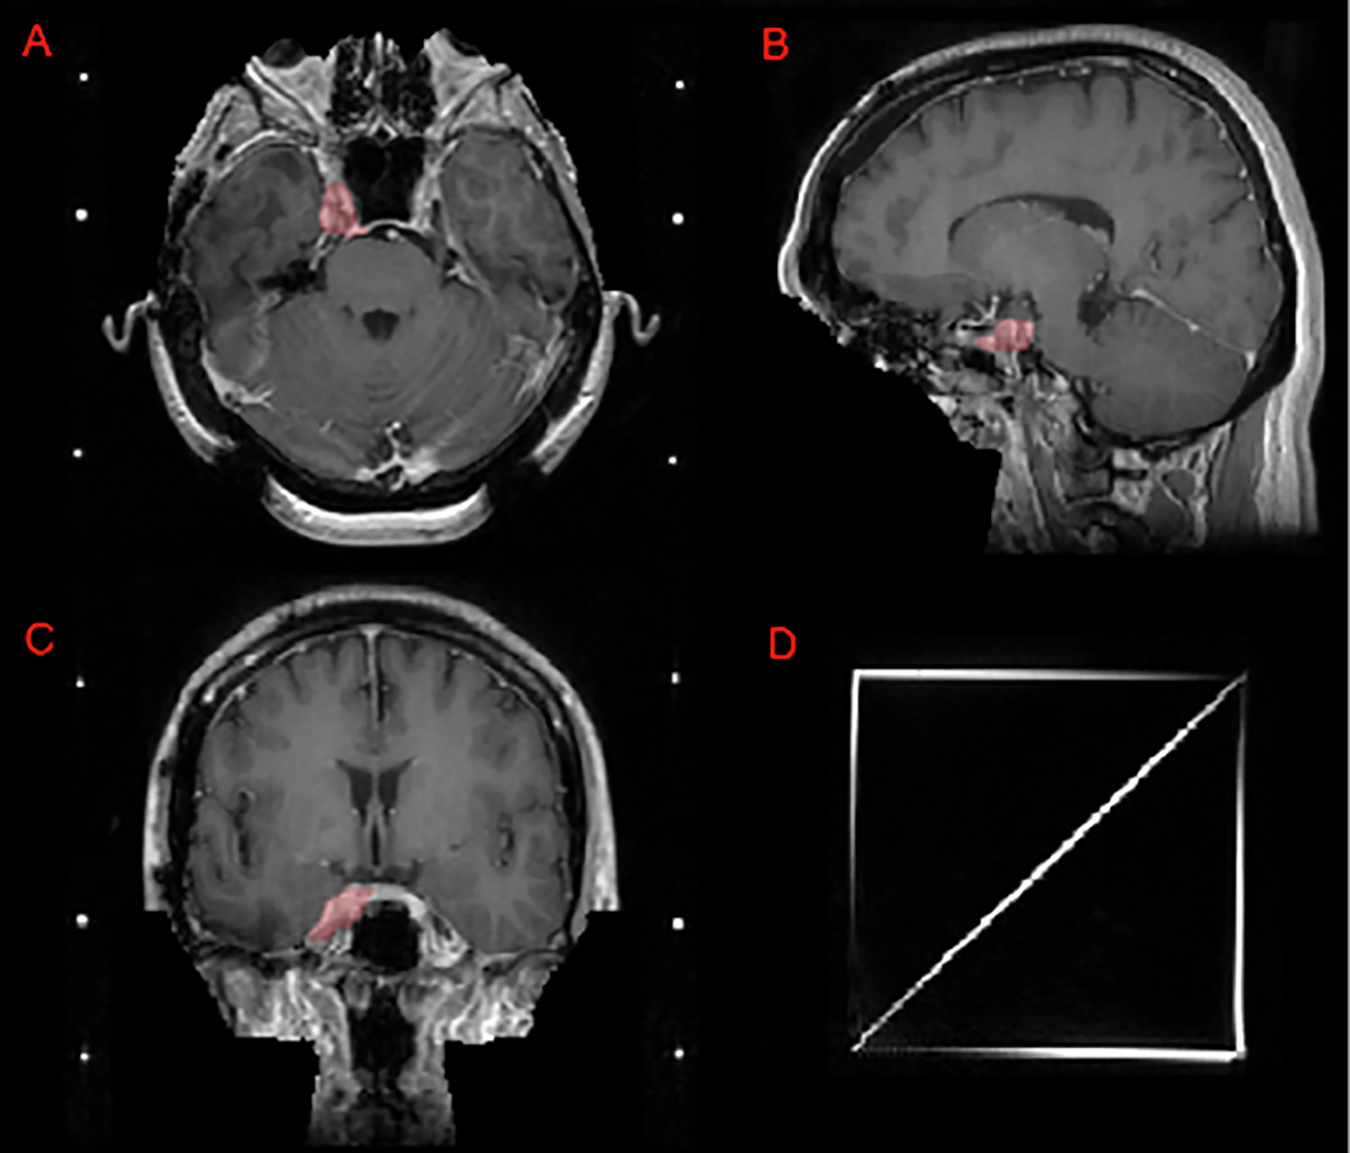

Fig. 7

From: The 2024 Brain Tumor Segmentation Challenge Meningioma Radiotherapy (BraTS-MEN-RT) dataset

Image panels depicting a case that utilizes a SRS planning Gamma Knife headframe. Panels A, B, and C depict an intact meningioma (red) in the right Meckel’s cave on T1c axial, sagittal, and coronal images, respectively. Note that this challenge’s defacing technique preserves this meningioma as compared to a skull-stripping pre-processing technique which would have excluded at least part of this lesion. Panel D shows the SRS localizer box fiducials attached to a standard Gamma Knife headframe.